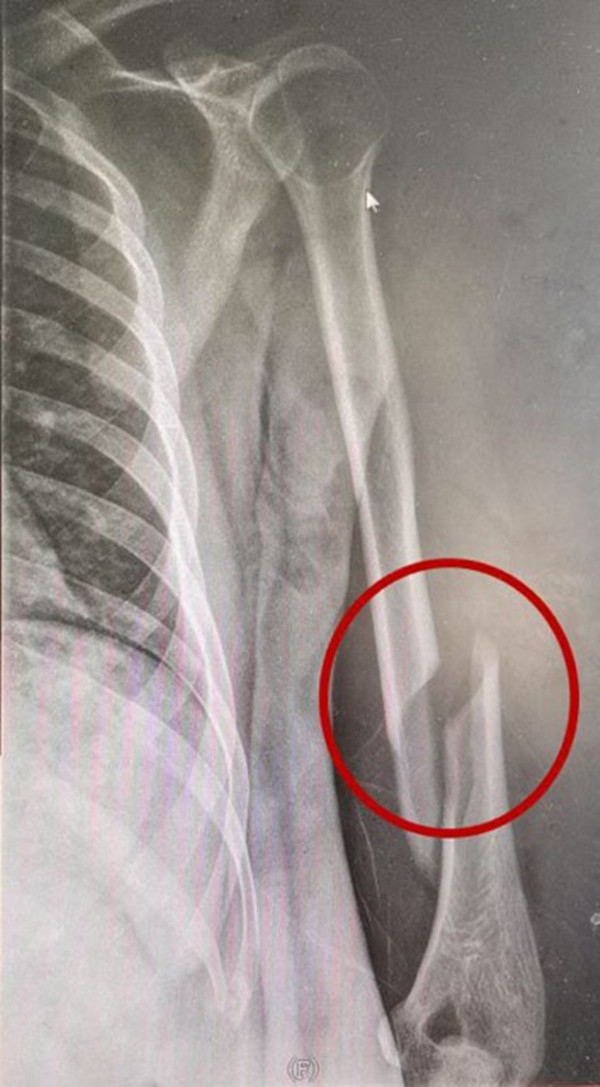

最近,小周的好友小张从内蒙古来宜兴游玩,因为两人都爱好健身,小张提议两人比试一下扳手腕,看看谁力气大。小周二话没说就答应了,正当两人相持不下时,只听“咔嚓”一声,小周当即感觉左上臂疼痛,使不上劲。在场的朋友都以为是桌腿断了,听到小周喊疼,才知道大事不好,赶紧送小周到宜兴市中医医院急诊。急诊外科医生接诊时,小周左上臂肿胀,压痛明显,急诊X线检查显示:左肱骨骨折。骨伤科医生为小周实施了左肱骨骨折切开复位内固定术。出院时,医生叮嘱他短期内不要提重物,平时要注意功能锻炼。

无独有偶。不久前,15岁的小王也因和同学扳手腕太用力,导致肱骨骨折而住院手术治疗。

扳手腕是年轻人间常有的游戏,通常情况下不至于发生意外,那为什么小周和小王会骨折呢?宜兴市中医医院骨伤科十六病区主任汤俊连介绍说,扳手腕时,当一方想要扳倒对方,需要瞬间发出超过对方数倍的力量进行攻击。在这个过程中,上臂肌肉向上向外收缩,前臂肌肉向内向下收缩,两种相反的力同时作用在扭曲的手臂上。这时若遇到对方同等的力量相抗衡,巨大的力量冲击,很容易使上臂的肱骨出现螺旋形骨折,甚至造成前壁骨折等情况。